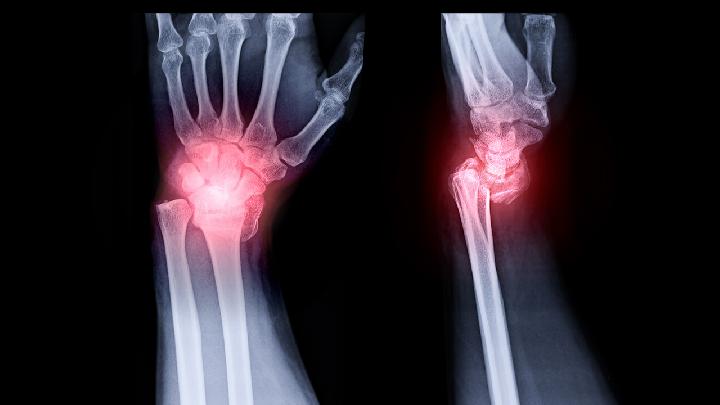

腕部损伤主要表现为骨间肌、蚯蚓状肌、拇收肌麻痹、小指爪形手畸形、手指内收、外展障碍、Froment特别是小指感觉消失时,手尺侧半和尺侧的感觉障碍。肘部损伤除上述表现外,还有环和小指末节屈曲功能障碍。